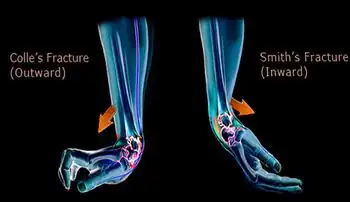

A Smith's fracture is a type of fracture of the forearm near the wrist in which the broken end of the radius is bent downwards.[1] The break is oblique, does not extend into the joint, and is associated with being pushed out of place.[2]

The distal fracture fragment is displaced volarly (ventrally), as opposed to a Colles' fracture which the fragment is displaced dorsally. Depending on the severity of the impact, there may be one or many fragments and it may or may not involve the articular surface of the wrist joint.

Smith vs Colles fracture.

Classic physical examination findings of a Smith's fracture is palmar displacement of the wrist that results in a "garden-spade deformity".